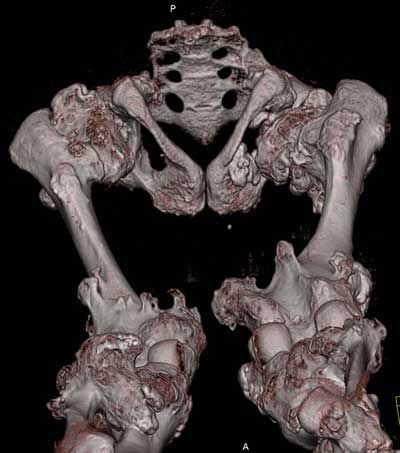

Oбратился больной 30 лет с хондродисплазией, множественными деформациями и экзостозами. Сгибательно-приводящие контрактуры Т/Б сустав, поясничный лордоз.

Интелектуально развит, работает програмистом. Болей нет. Анализы крови в пределах нормы, понижен кальций (общий Ca 1.62, N от 2.3 до 2.75;ионизорованный 0.67, N от 0.7 до 1.07) и щелочная фосфотаза -7.9. По данным КТ, оптическая плотность диафизов 150 - 200 NU (N в его возрасте 300 -350NU) метафизарный остеопороз от 100NU до отрицательных величин - 80 NU.

30 years old male with chondrodysplasia and multiple exostoses admitted.Multilevel deformities, flexion-adduction limitation of hip ROM, lumbar lordosis. Intellectually developed, working in some software company. Painless. Blood tests are normal, except low Calcium (total serum Ca 1. 62, N is 2.3 - 2.75; ionized 0.67 N is 0.7 -1.07) and low alkaline phosphatase 7.9. Diaphysis bone density is about 150 - 200 NU (N in his age is 300 - 350NU). Metaphis osteoporosis is from 100NU to minus 80 NU.

The x-ray is satisfactory for analysis. In The AP view, The knee and ankle should be exactly anterior and the patella should be facing forward, then we can measure the deformity in the AP. Another lateral view of the whole lower limb should be taken, so we can correct 6 dimensions (X, Y and Z axes and Alpha, Beta and Gamma rotation).

But it seemes to me that he has distal femoral valgus and may be also distal tibial. But anyway, we have to measure a good x-ray (lateral distal femoral angle, Medial proximal tibial angle and also the distal tibial angles).

Somtimes there are many deformities in the same lower limb. I do not like to make it sophistacted and correct everything, but just correcting the biggest deformity will make the alignment much better and the patient will be happy with the least risk and least duration of operation.

After Dr Elbatrawy saw the CT scans he added - the case has multible exostosis and the ulna also may need lengthening on both sides; he will need follow up, as one of the multible exostosis may transform to Chondrosarcoma on top of its cartilagenous cap. It is a common problem associated with this condition.